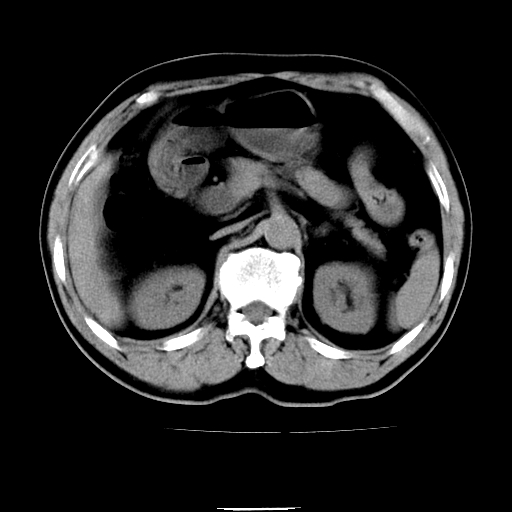

以下是引用chenqiong在2010-3-25 20:56:00的发言:[br]1、胆囊炎,胆囊息肉[br]2、肝内胆管及胆总管扩张,胆总管下端结石[br]3、十二指肠乳头旁憩室

以下是引用zxl51642在2010-3-26 10:47:00的发言:[br]胆囊炎,胆囊息肉,胆总管扩张,但未看到明显肿块,肝内胆管扩张不像恶性,炎性狭窄或阴性结石可能吧,建议mrcp,右肾小囊肿